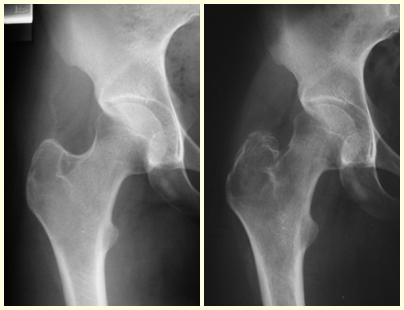

Radiológicamente se describe como una lesión epifisaria caracterizada por rarefacción ósea, inicialmente excéntrica, respetando inicialmente los límites corticales. A medida que avanza, puede producirse rotura cortical y afectación articular (fig. 27).